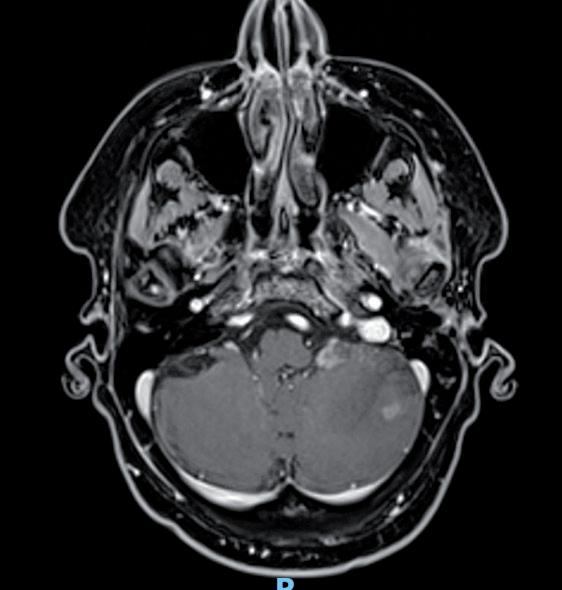

Tuttavia, nonostante la buona risposta iniziale, la TC total body con mezzo di contrasto del 28/12/2023 (figura 1) evidenzia progressione epatica ed encefalica con un quadro radiologico che mostra sovvertimento encefalico diffuso caratterizzato da numerose lesioni secondarie (almeno 10) a netta impregnazione contrastografica a sede sia cerebrale che cerebellare, prevalentemente subcentimetriche, la maggiore di 13 mm in nucleo-capsulare sx con nucleo necrotico e modesto alone edemigeno perilesionale.

La paziente, asintomatica sul piano neurologico e con marcatori tumorali negativi, viene sottoposta previo consulto multidisciplinare, a radioterapia panencefalica con risparmio dell’ippocampo con tecnica IMRT (30 Gy in 10 frazioni) e candidata poi a trattamento di II linea con T-DXd (5,4 mg/kg) q21, supportati dai dati di efficacia riportati dal DESTINY-Breast03, dalle analisi di sottogruppo degli studi DESTINY-Breast01, -02, -03 e dagli incoraggianti risultati preliminari degli studi DEBBRAH e TUXEDO-1.

La rivalutazione strumentale effettuata dopo 4 cicli di trattamento (figura 2) ha mostrato risposta intracranica completa ed epatica parziale. Lo studio della regione mammaria e ascellare con ecografia mammaria e mammografia ha mostrato assenza di lesioni infiltrative con presenza in sede retroareolare sx di un cluster di microcalcificazioni in assenza di linfoadenopatie ascellari. Lo studio tomografico con finestra per osso ha confermato la sovrapponibilità delle lesioni ossee rispetto alla precedente TC, in assenza di fratture patologiche. La paziente tuttora non ha mai manifestato eventi scheletrici secondari né riferisce dolore.